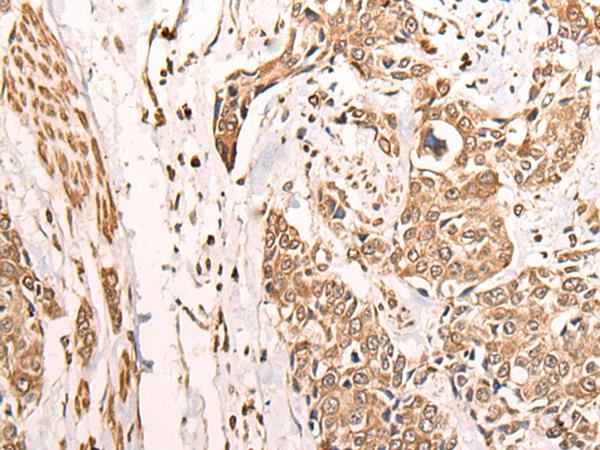

The image is immunohistochemistry of paraffin-embedded Human lung cancer tissue using (ATAD3A Antibody) at dilution 1/30. (Original magnification: ×200)

The image is immunohistochemistry of paraffin-embedded Human prostate cancer tissue using (ATAD3A Antibody) at dilution 1/30. (Original magnification: ×200)